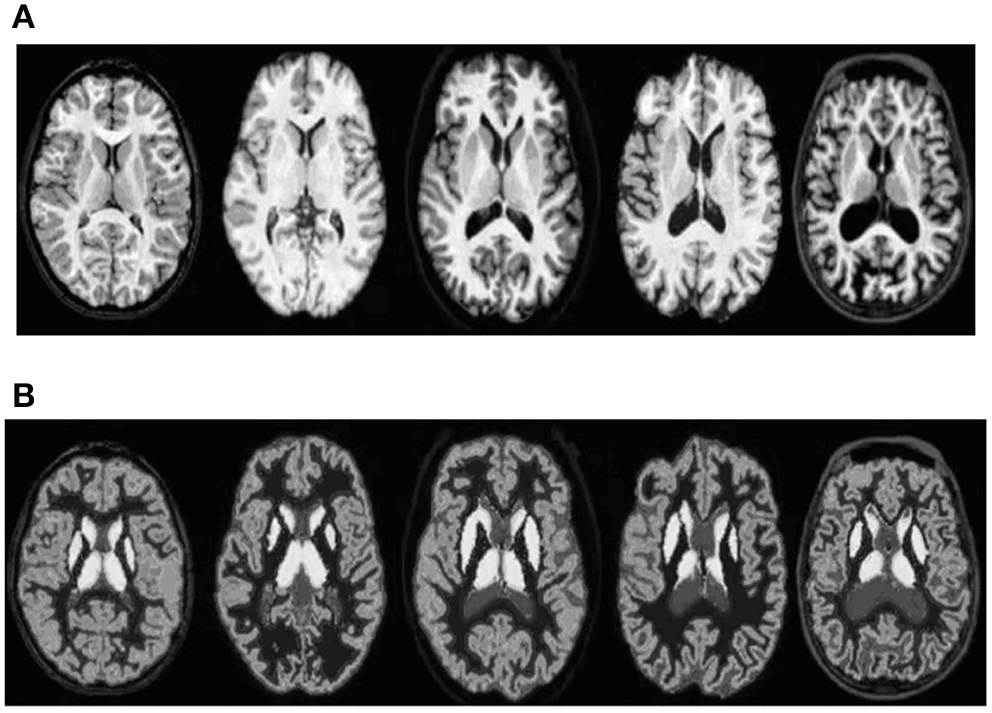

The proposed algorithm is used to segment the 3D multimodal medical images in the test set. Five brain images in the DeepLesion data set and three lung images in the SCR data set are selected for this study and the comparison of the effect pre- and postsegmentation is shown in Figures 2, 3.

Figure 2

Comparison of the effect of brain image segmentation before and after. (A) Presegmentation brain images. (B) Brain images postsegmentation by proposed algorithm.

According to Figures 2, 3, the application of the segmentation proposed algorithm can effectively achieve medical image segmentation. The image edge is clear for postsegmentation, the noise points can be effectively removed, and the definition is high.